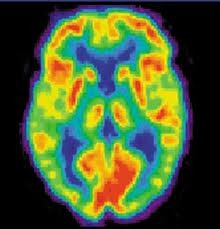

La TEP au FDG peut être utilisée pour le diagnostic précoce des maladies cérébrales dégénératives comme la maladie d’Alzheimer, la plus fréquente et la plus connue des démences.